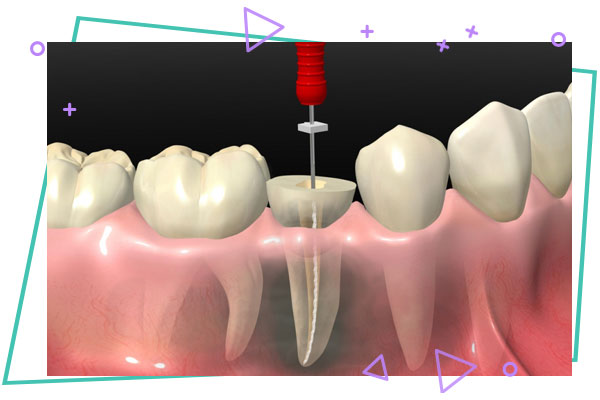

ابتدا پوسیدگی ها و عوامل عفونی در قسمت تاج دندان برداشته می شود . سپس کانال های ریشه دندان تعین طول شده و محتویات آن ها به وسیله ابزارهای سوهان مانند پاکسازی می شوند و در نهایت کانال های دندان بعد از شست و شو و ضد عفونی با مواد شبیه پلاستیک که از صمغ یک نوع گیاه تهیه شده اند و کاملا با بدن انسان سازگارند ، پرشده و مهر و موم می گردند .

امروزه در درمان های جدید به جای فایل دستی از فایل روتاری همراه با موتور استفاده می گردد ، که میزان پاکسازی کانال را افزایش داده و از زمان درمان می کاهد . اغلب درمان ها طی یک جلسه به پایان می رسد .